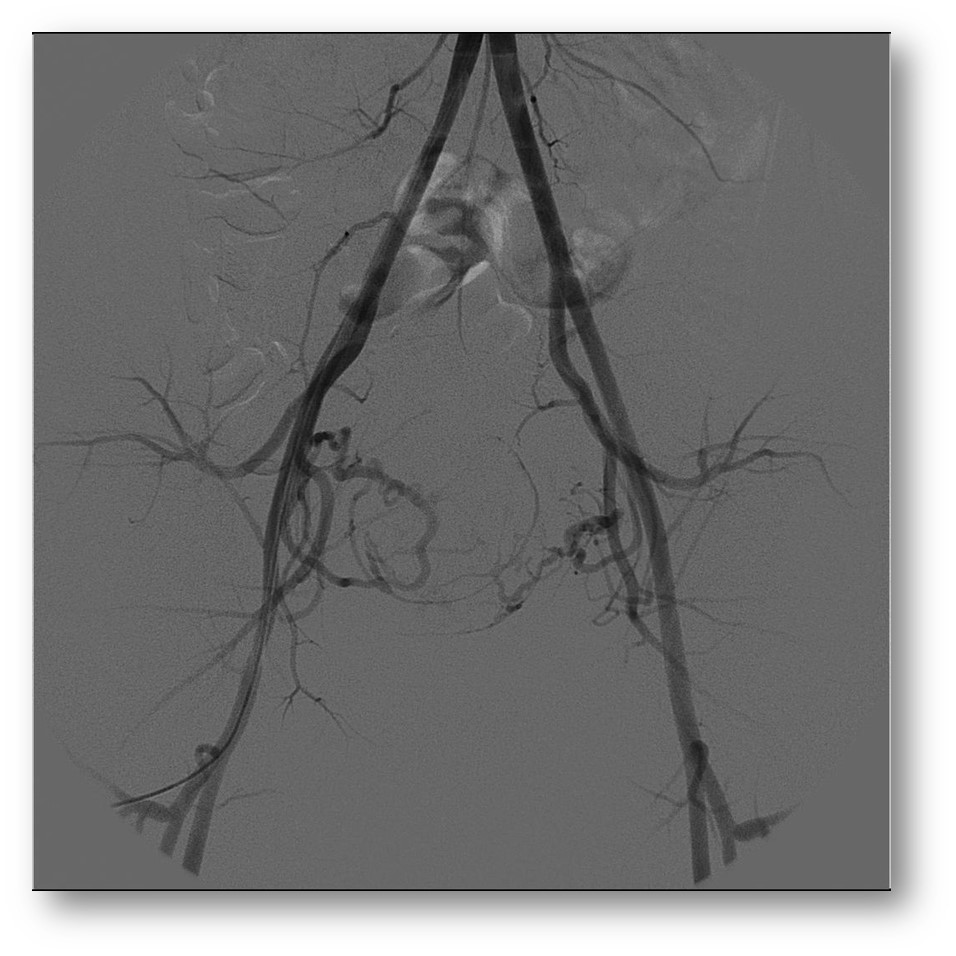

Esta imagem mostra

uma arteriografia de todos os vasos da pelve. Nela, o médico consegue

identificar as artérias que levam sangue e nutrem os miomas